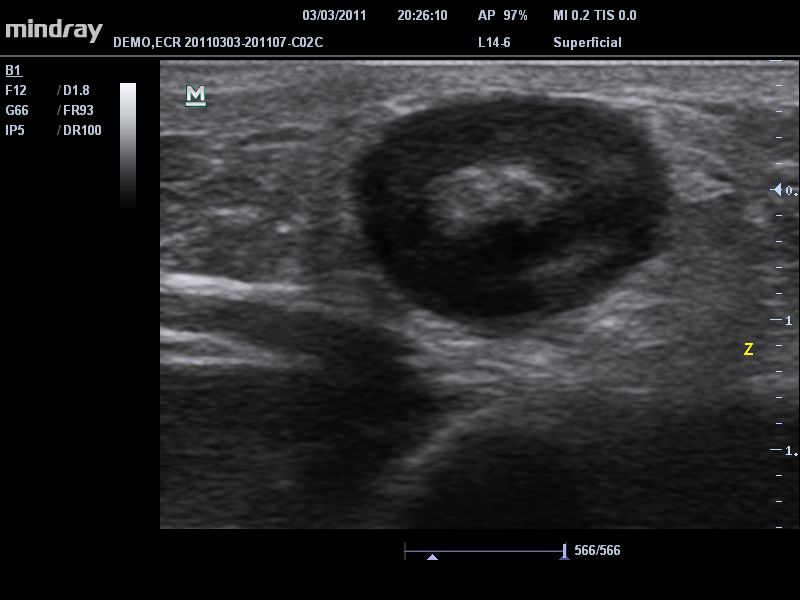

• Микроконвексный датчик Mindray 6C2

• Высокочастотный линейный датчик 38 мм Mindray l14-6NE